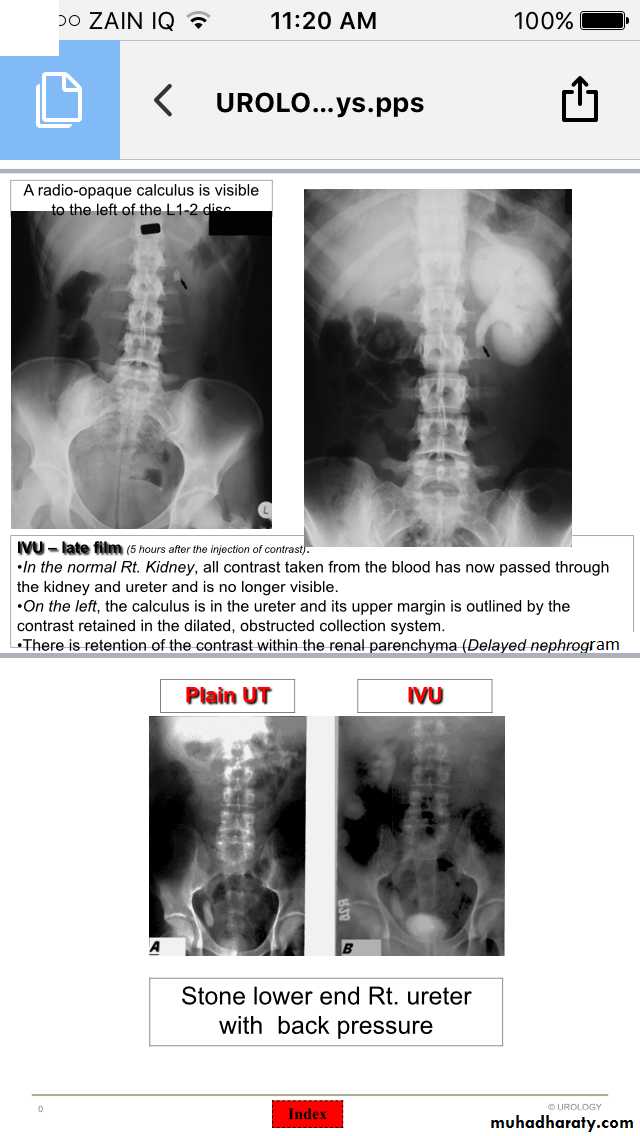

IVU

Ureteric stones

Hydronephrosis-Hydroureter